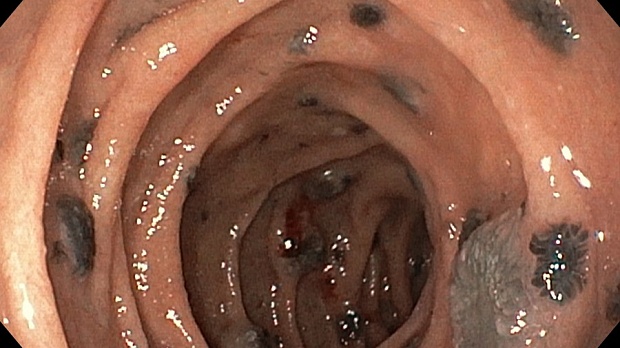

меланома ДПК.jpeg)

меланома ДПК.jpeg)

меланома ДПК.jpeg)

меланома ДПК.jpeg)

Эзофагогастродуоденоскопия диагностическая

12-кишка: Просвет луковицы двенадцатиперстной кишки обычный, содержит небольшое количество желчи, перистальтика активная , слизистая оболочка розового цвета, ворсинки сохранены. Так же прослеживаются пигментированные образования от 2мм до 8мм. серо-синюшного оттенка. Постбульбарном отделе множественные пигментые образования до 10мм, единичные кратообразные пигментные образования до 15мм, глубиной до 5мм., дно покрыто серым фибрином. Биопсия 2-а кусочка.

Заключение: ГПОД. Грыжевая гастропатия. Эрозивная гастропатия антрального отдела желудка. MTS Меланома ЛДПК, залуковичного отдела. Биопсия.